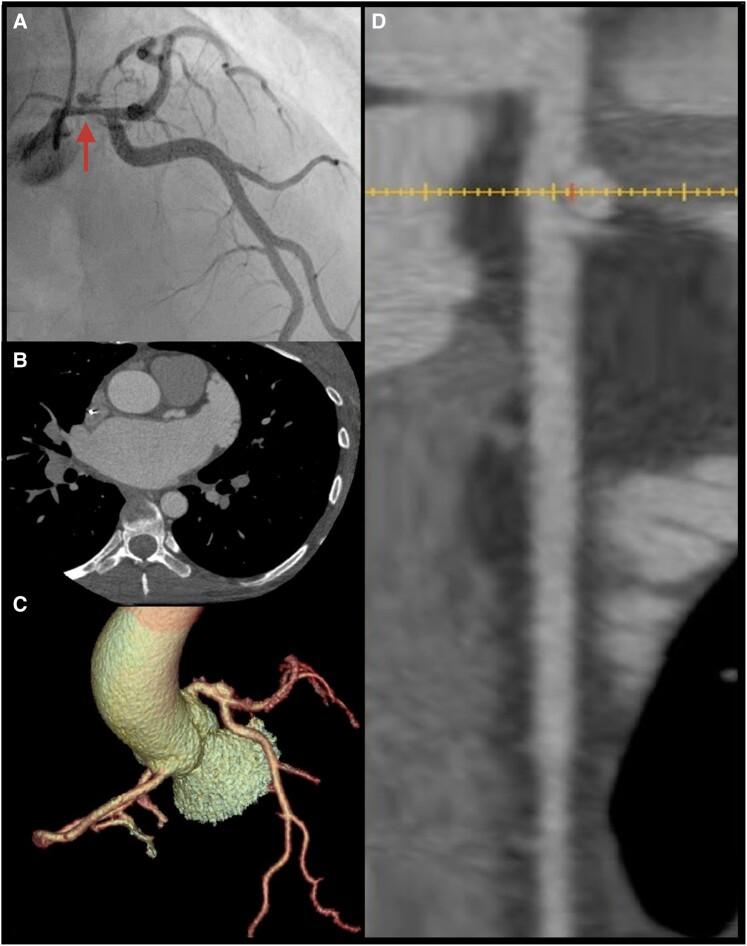

A previously healthy 39-year-old woman experienced sudden severe chest pain, ST-segment elevation on electrocardiogram, necessitating high-dose aspirin and urgent transfer to a revascularization centre. Suffering ventricular tachycardia (VT) and ventricular fibrillation (VF), she underwent two rounds of advanced life support and venoarterial extracorporeal membrane oxygenation. Diagnosed with left main coronary artery (LMCA) SCAD, she was initially started on conservative therapy for declining left ventricular ejection fraction. However, she continued to experience an escalating anginal symptoms, worsening biomarkers, and LMCA SCAD progression, which urged the need for surgical intervention with coronary artery bypass graft surgery (CABG). Following her CABG, she experienced a worsening of her functional mitral regurgitating, which she underwent transcatheter edge-to-edge repair of her severe mitral regurgitation. Despite being listed for orthotopic heart transplantation (OHTx), her low body mass index and elevated antibodies necessitated the HeartMate III left ventricular assist device (LVAD) for bridge to transplant. After treating frequent VT episodes with medications, she eventually received a LVAD as a bridge to cardiac transplantation. Within 1 year of her receiving LVAD, she underwent a successful OHTx.

一名既往健康的39岁女性突发严重胸痛,心电图显示ST段抬高,需要大剂量阿司匹林治疗并紧急转至血管重建中心。她出现室性心动过速(VT)和室颤(VF),接受了两轮高级生命支持和静脉-动脉体外膜肺氧合治疗。诊断为左主干冠状动脉(LMCA)SCAD,最初因左心室射血分数下降开始接受保守治疗。然而,她持续出现心绞痛症状加重、生物标志物恶化以及LMCA SCAD进展,这促使需要进行冠状动脉旁路移植术(CABG)手术干预。CABG术后,她的功能性二尖瓣反流恶化,因此接受了经导管二尖瓣缘对缘修复术治疗严重二尖瓣反流。尽管被列入原位心脏移植(OHTx)名单,但她的低体重指数和抗体升高使得需要使用HeartMate III左心室辅助装置(LVAD)作为移植桥梁。在用药物治疗频繁发作的VT后,她最终接受了LVAD作为心脏移植的桥梁。在接受LVAD的1年内,她成功接受了OHTx。